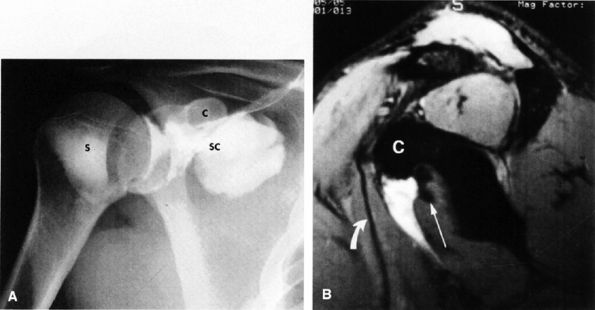

muscle. Glenohumeral joint version or humeral retroversion projects the axis of the humeral head joint surfaces 25° to 40° from the coronal plane, whereas the glenoid surface is retroverted 4° to 12° with respect to the scapula.46 The glenoid labrum, wedge-shaped in cross-section, is a ring of fibrous tissue with transitional fibrocartilage attached to the margin of the glenoid cavity.47 Labral tissue deepens the depression of the glenoid fossa and enlarges the glenohumeral socket contact area (Figs. 8.58 and 8.59).